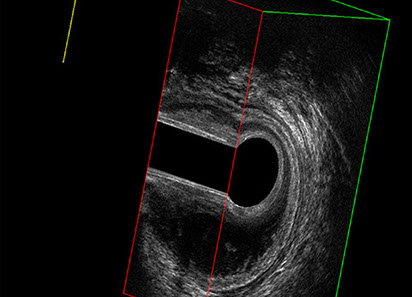

Sezione Longitudinale 3D con Tramite Fistoloso Intersfinterico Basso Anteriore Semplice

L’ecografia transanale è un esame diagnostico per immagini che consiste nell’introduzione di un trasduttore ad ultrasuoni. Le immagini qualitativamente migliori del canale anale sono ottenute usando un trasduttore rotante, montato in un manipolo rigido, che fornisce un’immagine a 360°. Con le apparecchiature più moderne è anche possibile ottenere immagini tridimensionali.

Proctal dispone di apparecchiatura per ecografia endoanale 3D con sonda rotante.